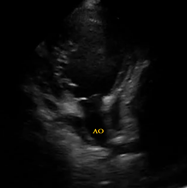

Il s’agit d’un enfant âgé de 3 ans qui s’est présenté pour une dyspnée d’effort associée à une toux sèche, L’examen a objectivé un tableau d’insuffisance cardiaque globale avec un souffle systolique au foyer mitral. L’enfant est adressé pour réalisation d’une échographie cardiaque :

Il s’agit de :